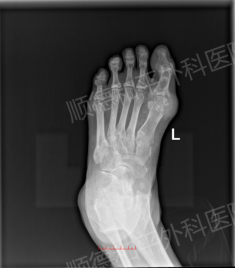

病例回顾: 患者林先生,年轻(33岁)但病史已达4年,痛风石已影响手指关键功能且造成外观困扰。手部结构精细,神经、血管、肌腱密布,对手术的精准度要求极高。

视野清晰放大: 在显微镜的高倍放大下,医生能清晰分辨出乳白色的尿酸盐结晶与正常的肌腱、韧带、神经组织,仿佛在“显微镜下挖土豆”。

精准彻底清除: 对于林先生手指关节内的痛风石,医生可以做到颗粒归仓式清除,不遗漏任何微小结晶。这不仅最大程度地解除了对神经、肌腱的压迫,恢复了手部精细功能,更从根源上减少了因残留尿酸盐结晶而导致的术后复发风险。同时,精准操作也保障了术后手部的美观性。